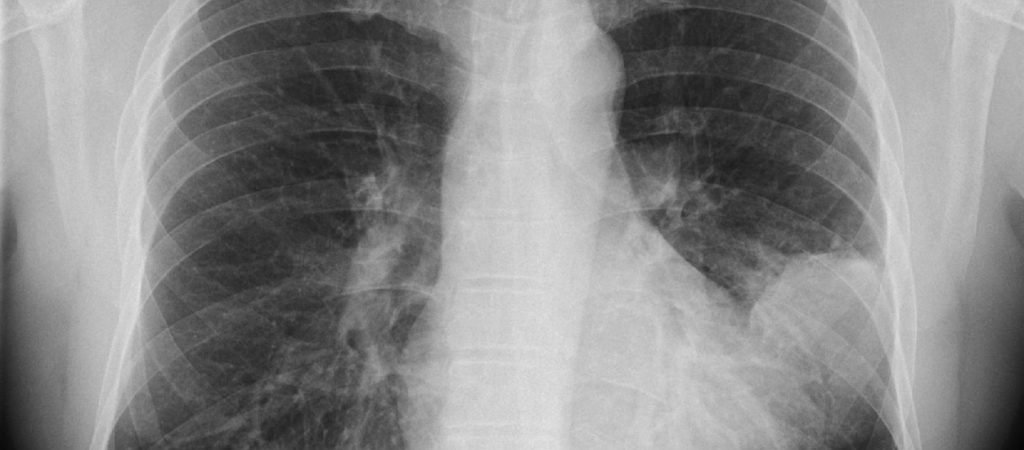

In Industrienationen gilt die Lungenentzündung (Pneumonie) als häufigste tödliche Infektionskrankheit. Alleine bei der Diagnose "Lungenentzündung" erschrecken viele. Viele Schulmediziner…

Die Tuberkulose (Tbc) ist eine durch Mykobakterien ausgelöste Infektionskrankheit vornehmlich der Lunge (85 Prozent). Nahezu ein Drittel der Weltbevölkerung trägt den Erreger in sich, der bei…

Das Lungenemphysem beschreibt eine krankhafte, irreversible Destruktion (Zerstörung) durch Überblähung unterhalb der terminalen Bronchien. Hiervon zu unterscheiden ist das plötzlich auftretende (reversible)…

Der Lungenhochdruck (pulmonale Hypertonie = PH oder PAH für pulmonale arterielle Hypertonie) ist eine seltene Erkrankung der Gefäße des Lungenkreislaufs, bei der…

COPD (chronic obstructive pulmonary disease = chronisch-obstruktive Lungenerkrankung) ist eine Erkrankung der Lungen, die sich meist aus der chronischen Bronchitis entwickelt und zu entzündeten und…

Die bronchopulmonale Dysplasie tritt bei nahezu 30 Prozent aller Früh- und Neugeborenen mit einem Gewicht unterhalb 1.000 Gramm auf. Vermutet werden vor allem entzündliche Prozesse, die dazu führen, dass die Lungen…

Bei einer Bronchitis handelt es sich um eine Lungenkrankheit, die mit einer Entzündung der verzweigten Atemwege (Bronchien), Husten, Schleimauswurf (weißlich bzw. gelb-grünlich) und Fieber einhergeht.

Asthma ist eine chronische Atemwegskrankheit. Erstmals verwendete Hippokrates den griechischen Begriff „astmaois“, das heißt „keuchen“. Asthma kann in anfallsartigen Schüben zu schwerster Atemnot führen,…

Die im Thorax (Brustkorb) liegende Lunge (Pulmo) zählt zu den Atmungsorganen und setzt sich aus zwei Flügeln zusammen. Die rechte Lunge besteht aus drei Lappen (Lobi), die linke aus zwei, wobei…